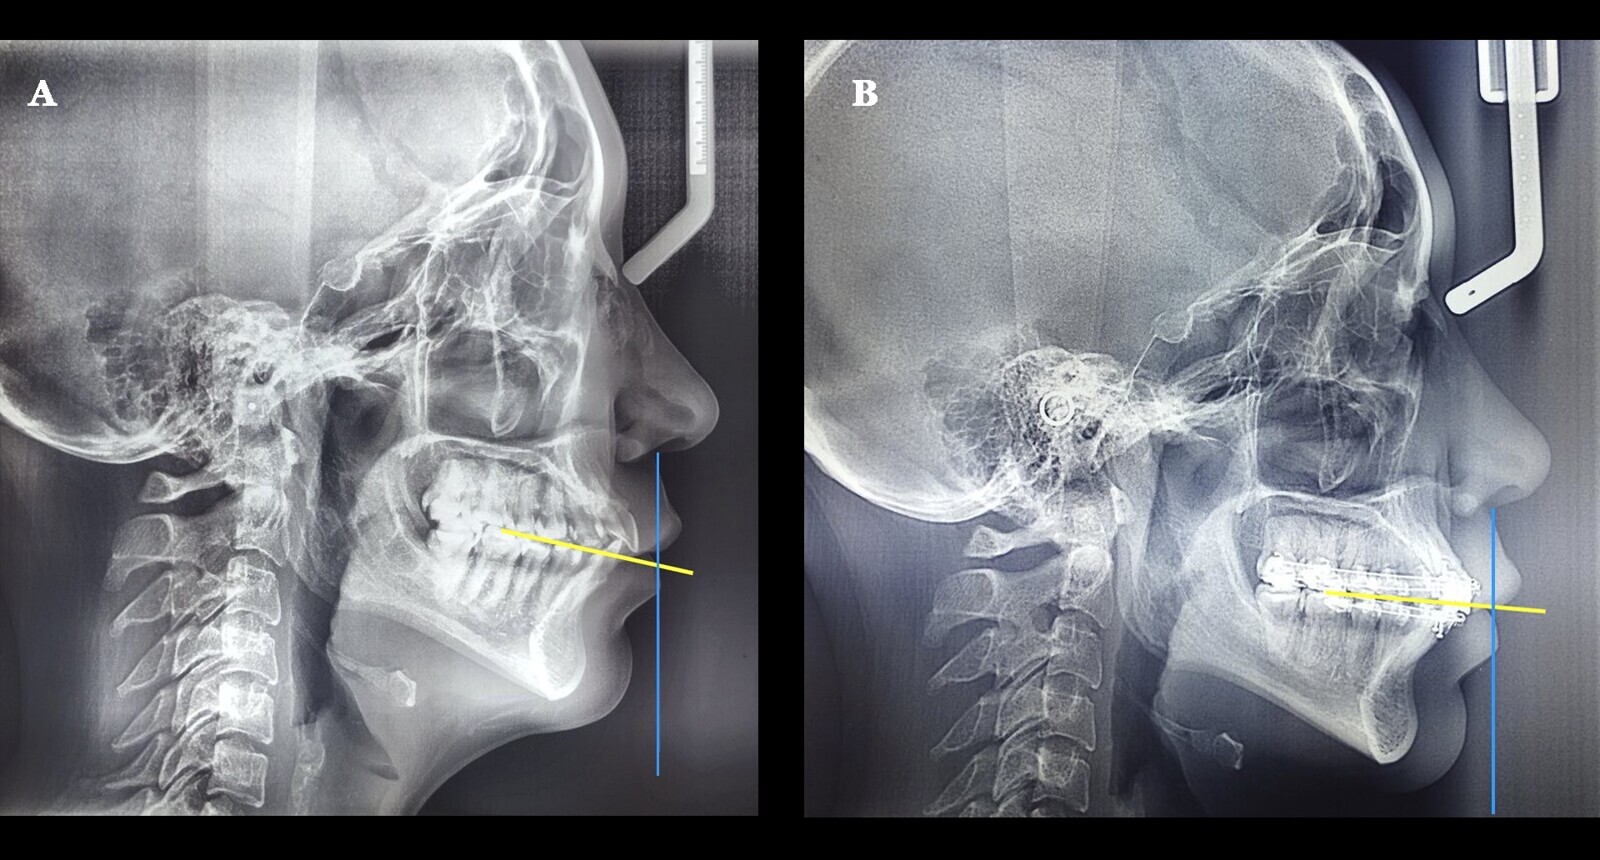

Figura 4. A) Telerradiografía de perfil inicial que muestra el plano oclusal inclinado. B) Telerradiografía de perfil final de la mejoría del plano oclusal, habiendo rotado en sentido antihorario.